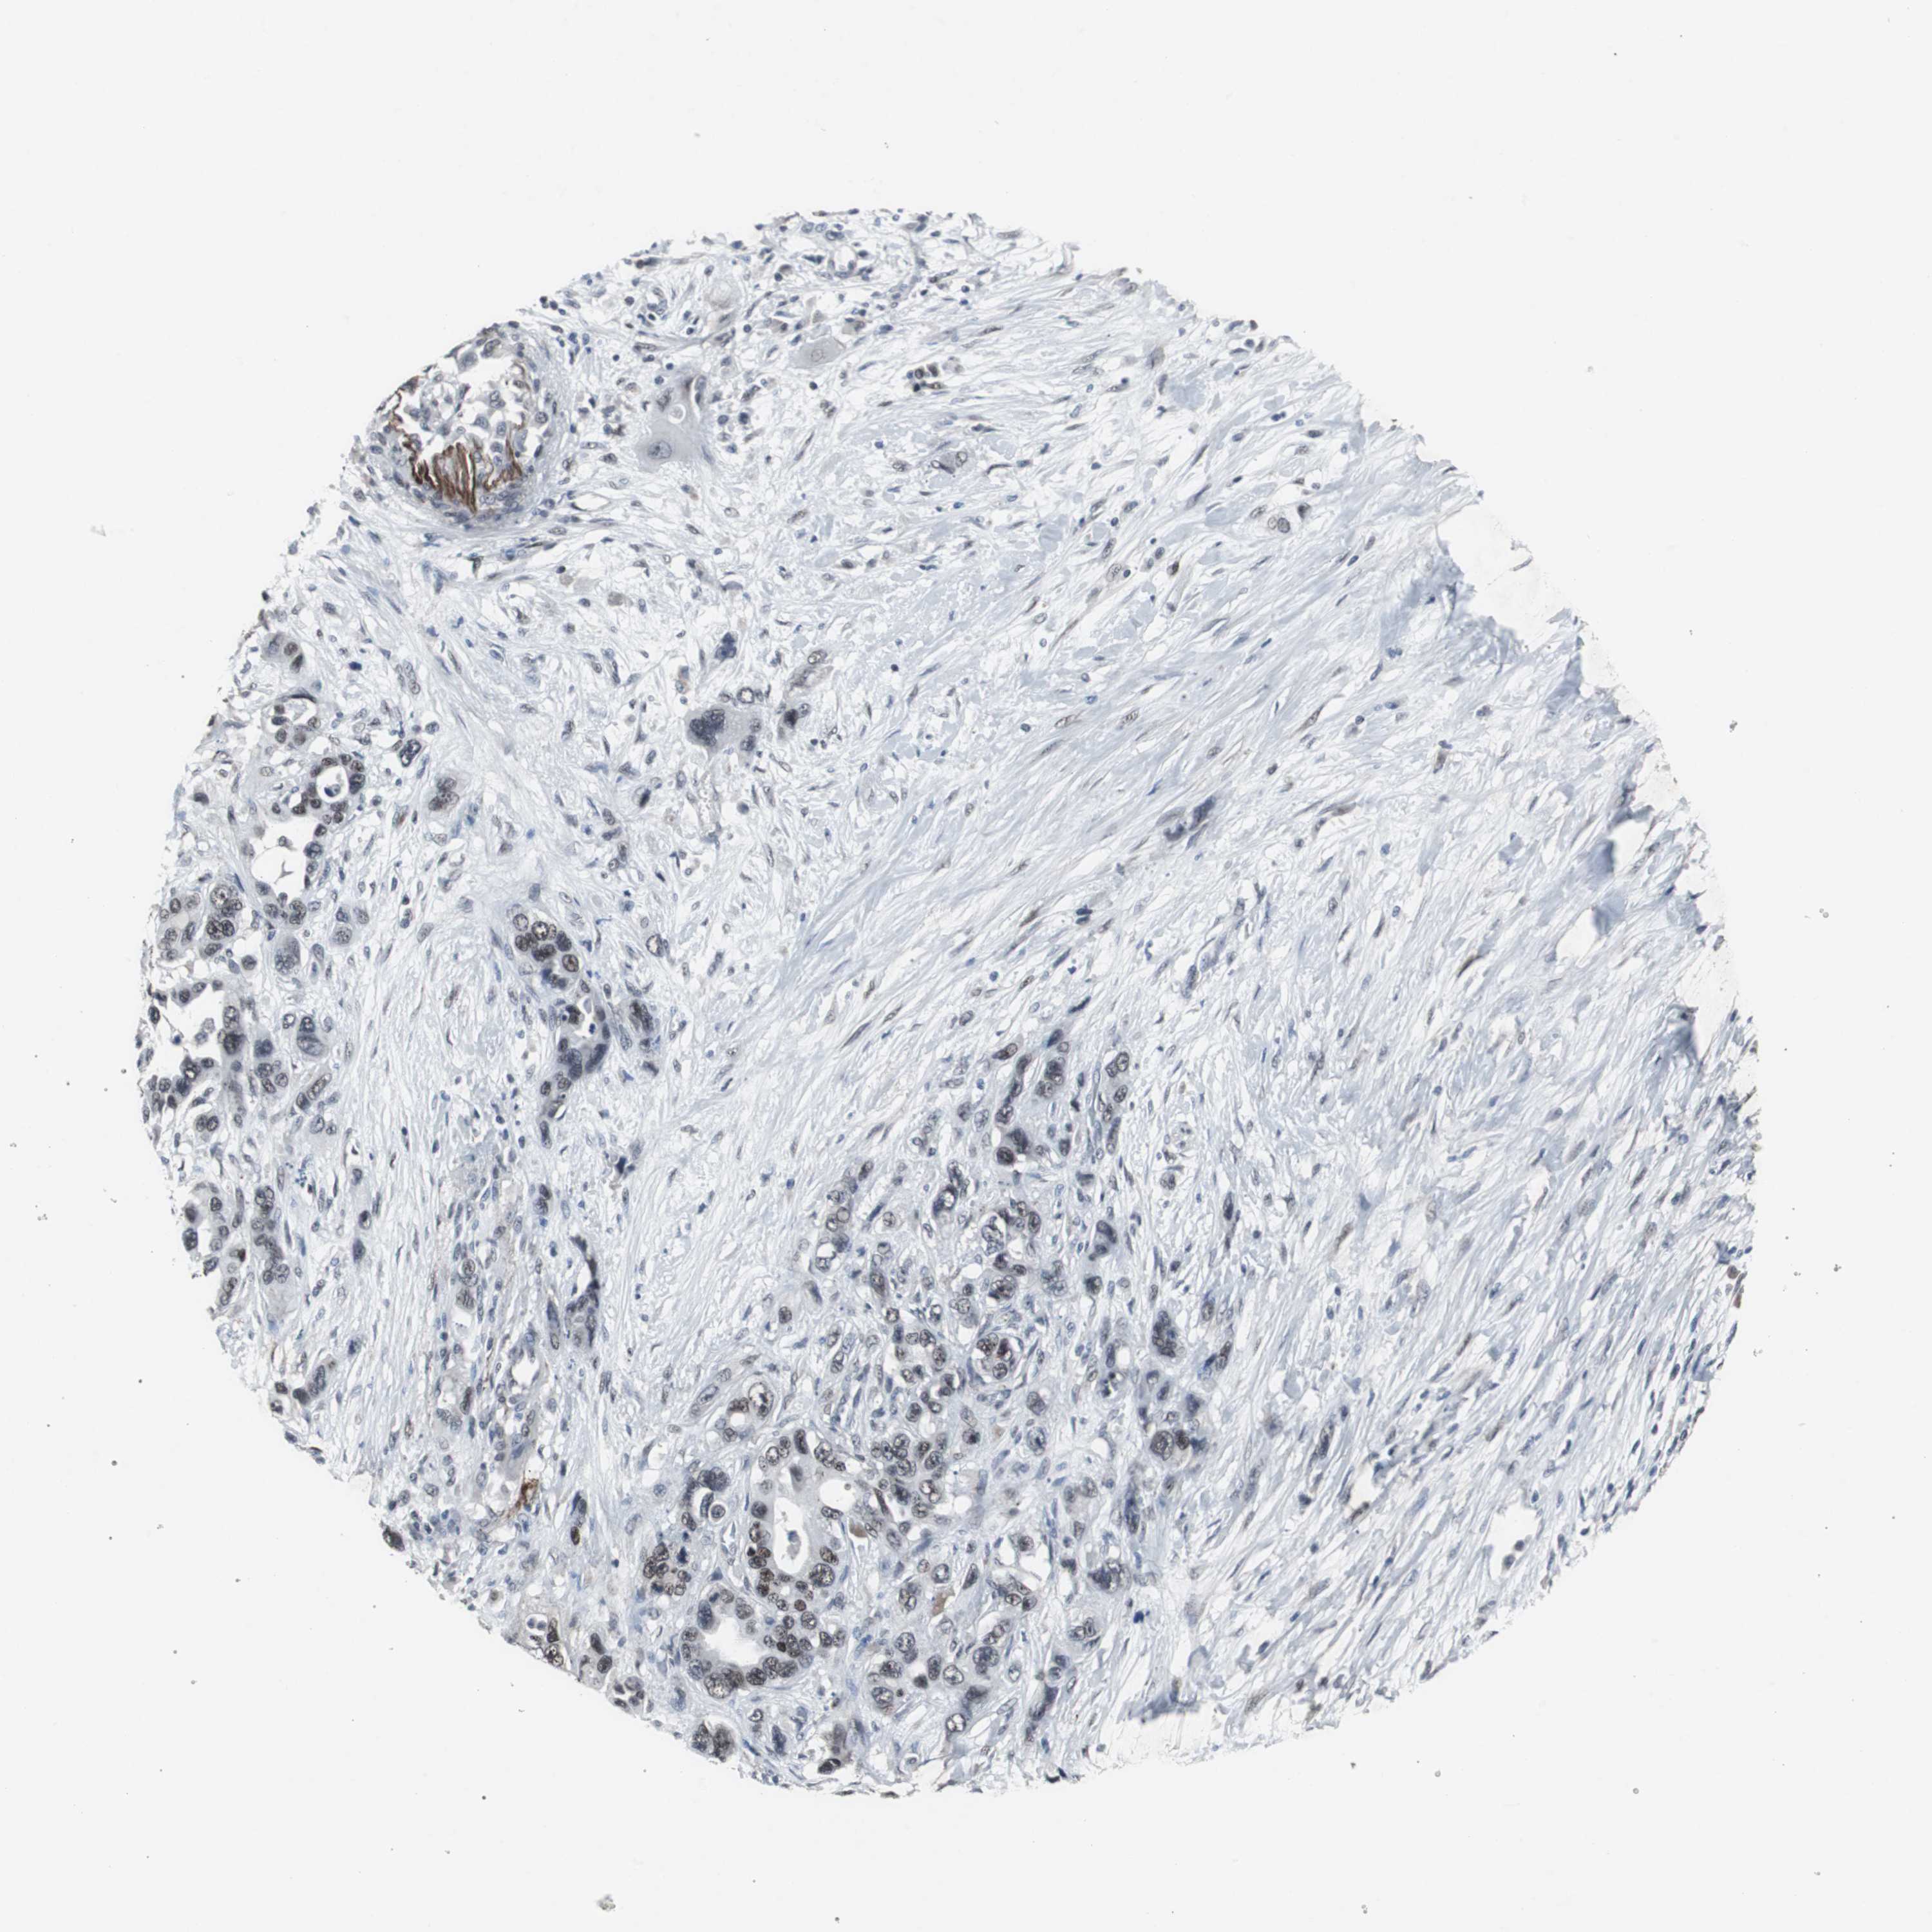

PANCREATIC CANCER - Protein expressioni

A mouse-over function shows sample information and annotation data. Click on an image to view it in a full screen mode. Samples can be filtered based on level of antibody staining by selecting one or several of the following categories: high, medium, low and not detected. The assay and annotation is described here.

Note that samples used for immunohistochemistry by the Human Protein Atlas do not correspond to samples in the TCGA dataset.

Antibody stainingi

Antibody staining in the annotated cell types in the current human tissue is reported as not detected, low, medium, or high, based on conventional immunohistochemistry profiling in selected tissues. This score is based on the combination of the staining intensity and fraction of stained cells.

Each image is clickable and will lead to virtual microscopy that enables deeper exploration of all samples and also displays staining intensity scores, fraction scores and subcellular localization as well as patient and tissue information for each sample.

Antibody HPA007176

Staining

High

Medium

Low

Not detected

Intensity

Strong

Moderate

Weak

Negative

Quantity

>75%

75%-25%

<25%

None

Location

Nuclear

Cytoplasmic/membranous

Cytoplasmic/membranous,nuclear

Adenocarcinoma, NOS

Adenocarcinoma, metastatic, NOS